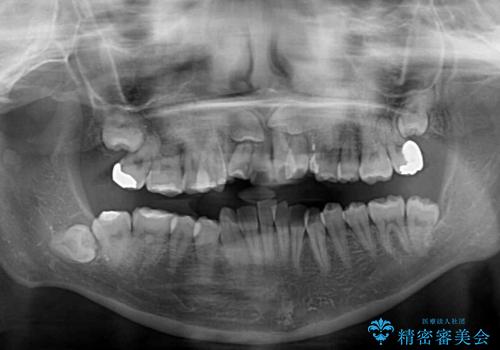

- 上下前歯のデコボコを気にして来院された患者様です。

上顎は両側の犬歯が骨内に埋伏しており、乳歯が残存している状態でした。

歯肉内に埋もれている場合には牽引することも可能ですが、両歯ともに骨内に完全に埋もれていたため、牽引することは不可能と判断しました。

口元の突出感があるわけではなく、叢生の程度もシビアではありませんでしたが、顎骨が小さく、左右ともに最後臼歯が歯肉に埋もれているため、下顎は左右第二小臼歯を抜歯することとしました。

上顎は左右ともに残存している乳歯を抜歯し、上下歯列を整えることとしました。